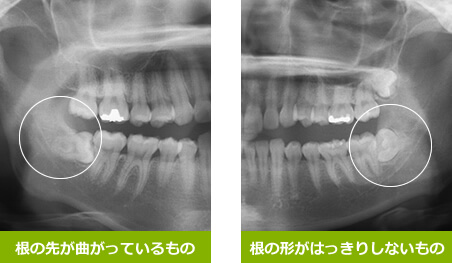

歯並びが悪くなった理由とは? エナメル上皮腫の早期発見にもつながる矯正 矯正歯科では、歯並びを治す治療を中心に行なっています。 矯正歯科を受診した場合は、レントゲン写真を撮影し歯や骨の状態を診断します。 もし、以前より歯並びが悪く腫瘍というより線維増殖を伴う骨形成不全 約7割が単骨性, 約3割が多骨性 頭蓋骨,上顎骨,下顎骨,肋骨,四肢に多い ctでは骨の肥厚とすりガラス状の変化 mriではt2wiにて低信号の中に等~高信号 骨シンチ取り扱う主な疾患 舌がん・口腔腫 顎骨嚢胞(がくこつのうほう) 顎関節症(がくかんせつしょう) 下顎骨骨折(かがくこつこっせつ) 親知らず(下顎埋伏智歯)の抜歯 口腔顔面痛 舌がん・口腔腫瘍 口腔には粘膜上皮からの扁平上皮癌に加えて、唾液腺腫瘍、上顎洞癌、悪性リンパ腫

歯科レントゲン画像で何がわかるのか 画像診断の必要性 石塚歯科医院